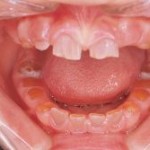

Dental manifestations of dentinogenesis imperfecta

-Â Â Â Â Â Â Â Â Â Clinically, your teeth may look amber, grey or purple bluish

-Â Â Â Â Â Â Â Â Â Enamel is poorly adherent to the underlying dentine, thus they are easily chipped off and wear.

-Â Â Â Â Â Â Â Â Â Radiographically, pulp chambers can be obliterated and crowns are bulbous.(initially they have large pulp chamber during eruption)

-Â Â Â Â Â Â Â Â Â Rapid wear of the dentine layer. This will cause loss of vertical dimension and early pulpal involvement.

-Â Â Â Â Â Â Â Â Â In general, there will be early loss of teeth.

-         Dentine of the involved teeth maybe exposed. However, patient will not complain of sensitivity due to sclerosis.